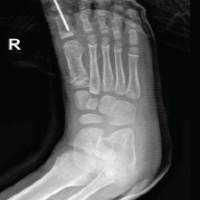

A 16-year-old boy presented to our outpatient department with a history of recurrent patellar dislocation in his right knee for the past 3 years. He also complained of a deformity of his right knee. On examination, his patella was grossly unstable, dislocating at about 30° of knee flexion (Fig. 1). Whole limb X-ray revealed a lateral mechanical axis deviation of 30 mm from the neutral (normal range – <10 mm) (Fig. 2). The opposite limb was normal. The Q angle of the right lower limb was measured to be 22°, which was abnormal (normal range 13–18°). The right knee was in valgus with a tibio-femoral angle of 15° (Fig. 3). The mechanical medial proximal tibial angle was 87.8° which was normal (normal range 85–90). However, the mechanical lateral distal femoral angle was 81°, which was abnormal (normal range 85–90) (Fig. 4 and 5). Hence, it was the distal femur that contributed to the genu valgum. The tibial tubercle–trochlear groove distance was 17 mm, which was normal (normal – under 20 mm), signifying that there was no rotational deformity. The Insall-Salvati ratio was 1.2, which was also normal (range – 0.8–1.2). Magnetic resonance imaging (MRI) revealed a Dejour Type D trochlea dysplasia (Fig. 6) with a trochlear depth of 1.2 mm (normal >3 mm) and a sulcus angle of 172 (normal <140). MRI also revealed an MPFL tear. The factors contributing to the patellar instability were recognized as the unacceptable genu valgum, trochlear dysplasia, and the MPFL tear. Considering that the patient had attained skeletal maturity and to avoid multiple procedures, a decision was made to correct all the anatomical abnormalities as a single procedure.

The valgus at the knee was corrected to neutral alignment (Fig. 10). The mechanical lateral distal femoral angle was corrected from 81° to 88° post-operatively. The trochleoplasty had increased the trochlear depth from 1.2 to 4 mm and the sulcus angle from 172° to 140° postoperatively (Fig. 11). The patient is currently at 1 year follow-up, and has attained full range of motion (Fig. 12). There has been no further episodes of patellar dislocation and the patient is leading an active lifestyle without apprehension or instability. The Tegner Lysholm knee score improved from a pre-operative value of 51 to a post-operative value of 94, and the Kujala knee score also showed improvement from 18 to 27 postoperatively (Fig. 13).